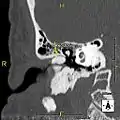

Exostosis in ear canal

The normal ear canal is approximately 7 mm in diameter and has a volume of approximately 0.8 ml (approximately one-sixth of a teaspoon).[4] As the condition progresses, the diameter narrows and can even close completely if untreated, although sufferers generally seek help once the passage has constricted to 0.5-2 mm due to the noticeable hearing impairment. While not necessarily harmful in and of itself, constriction of the ear canal from these growths can trap debris, leading to painful and difficult to treat infections.